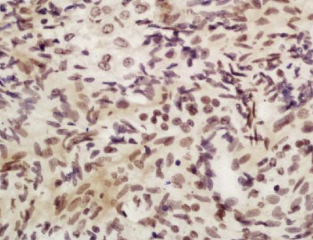

组织/细胞:大鼠卵巢组织;4%多聚甲醛固定石蜡包埋;

抗原提取:柠檬酸缓冲液(0.01M,pH 6),15min煮沸,用3%过氧化氢阻断内源性过氧化物酶30min;37℃下阻断缓冲液(正常山羊血清,C-00 05)20 min;

孵育:抗apobec3b多克隆抗体,未结合(BS-12494R)1:200,4°C下过夜,然后与二级抗体结合,DAB染色。